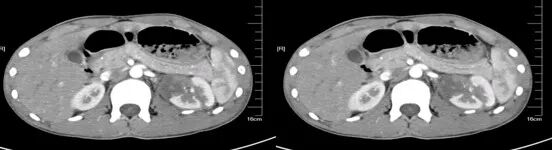

大肠癌

大肠癌是常见的恶性肿瘤,包括结肠癌和直肠癌。大肠癌的发病率从高到低依次为直肠、乙状结肠、盲肠、升结肠、降结肠及横结肠,近年有向近端(右半结肠)发展的趋势。其发病与生活方式、遗传、大肠腺瘤等关系密切。发病年龄趋老年化,男女之比为1.65:1。

升结肠癌并肝转移